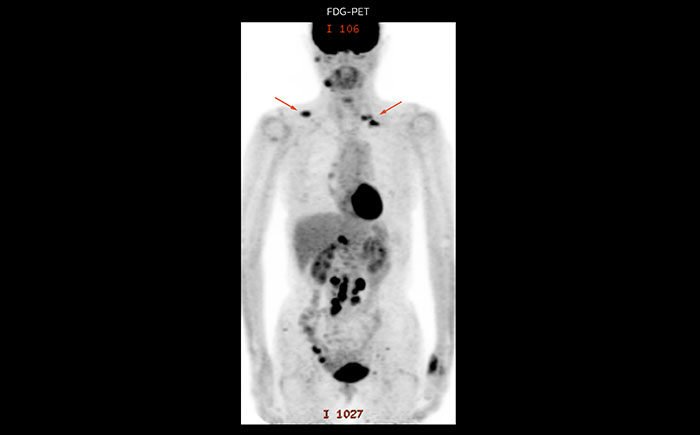

Whole body diffusion

A 61-year-old female with a malignant lymphoma underwent an MRI exam with whole body diffusion weighted imaging (DWIBS) as well as PET. On the images shown, the resolution of DWIBS is better than PET, which allows visualization of the small pelvic lesions and almost no distortion is seen in the neck area.

Whole body diffusion

A 61-year-old female with a malignant lymphoma underwent an MRI exam with whole body diffusion weighted imaging (DWIBS) as well as PET. On the images shown, the resolution of DWIBS is better than PET, which allows visualization of the small pelvic lesions and almost no distortion is seen in the neck area.